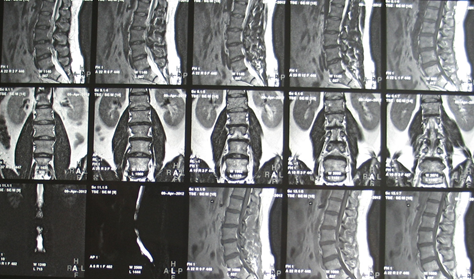

Отделы позвоночника для мрт схема фото и названия